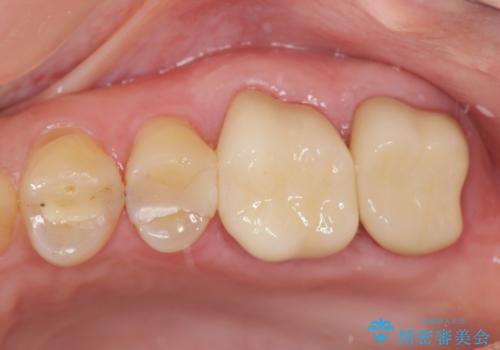

[ 歯肉縁下齲蝕 ] 歯周外科を行った虫歯治療

![[ 歯肉縁下齲蝕 ] 歯周外科を行った虫歯治療の症例 治療後](https://seimitsushinbi.jp/wp/wp-content/uploads/2023/05/fa1958073cf4724216bea0bd1890c46a-500x350.jpg?v=1684994581)